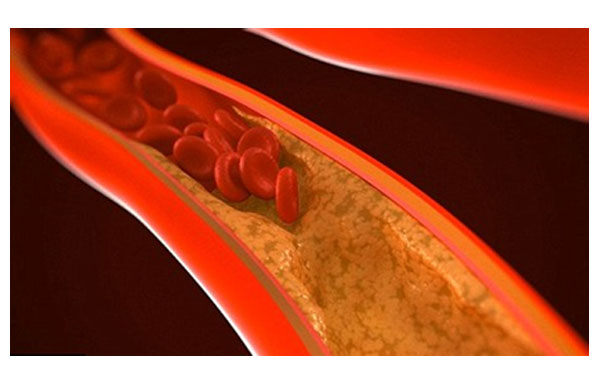

Non-Alcoholic Fatty Liver Disease is increasingly common worldwide and linked to obesity, diabetes, and metabolic syndrome. Recent research underscores that MASLD treatment centers on lifestyle modification and drug therapies targeted at metabolic risk factors.